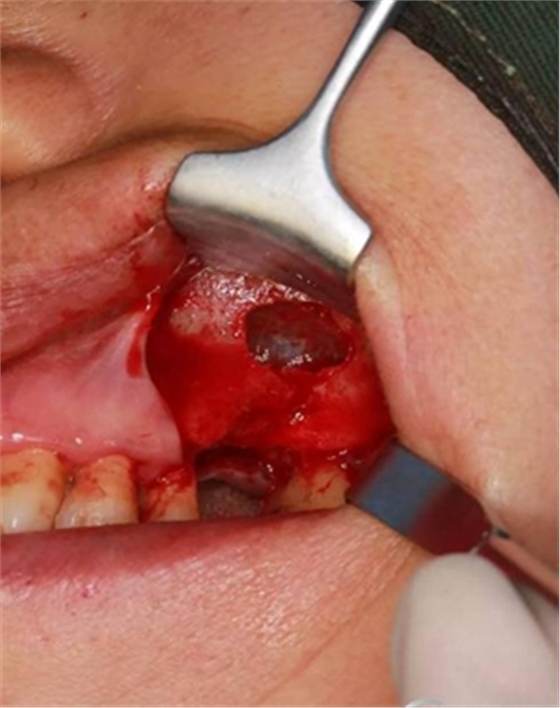

大家好,我是梁老師的助理小依。由于梁老師每天手術(shù)檔期安排較滿,加上經(jīng)常出差講課,沒有時間整理病例 。為了方便大家更及時的了解梁老師最新手術(shù)動態(tài),以后將由我為大家整理并推送梁老師最新經(jīng)典案例。案例文字旁白少,但圖片會盡量完整展示手術(shù)全過程,供大家學(xué)習(xí)參考。有任何問題,可以留言,梁老師會親自為大家解答。感謝大家對梁老師的支持和關(guān)注!